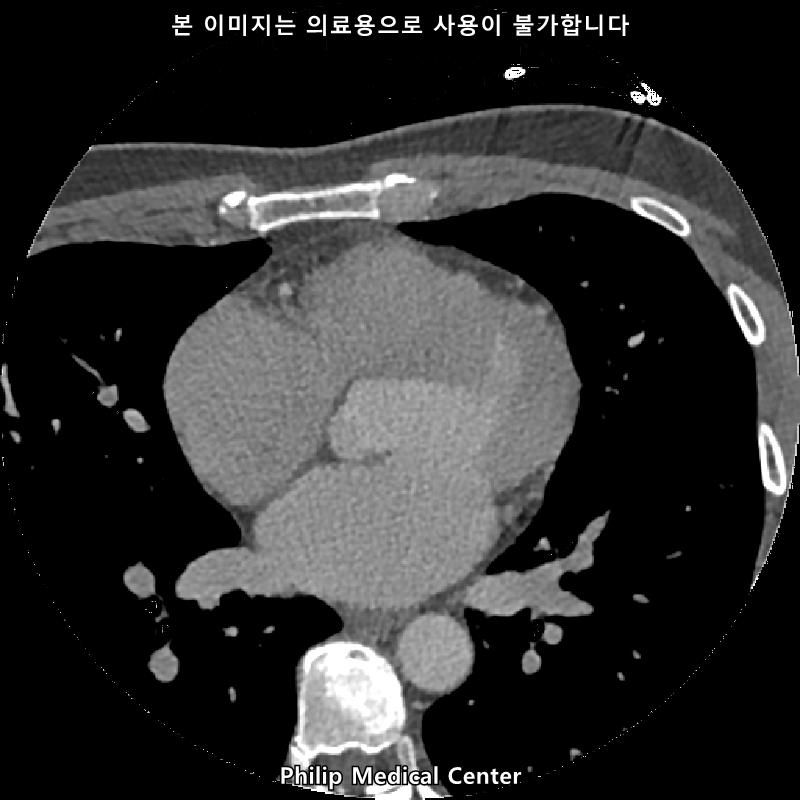

• 3번 째 사진

• 올리신 사진들을 통해서는 폐를 평가할 수 없습니다.

우측 폐첨부에 경미한 섬유성변화와 우중엽에 약 3mm크기의 결절이라는 것은 이상 소견이긴 하지만 보통 경과관찰을 하는 소견입니다.